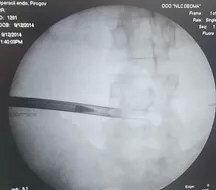

Рабочая канюля (порт) в область расположения грыжи позвоночника устанавливается под контролем рентгеноскопии в двух проекциях, что обеспечивает полную безопасность доступа к позвоночной грыже. Непосредственно во время операции удаления позвоночной грыжи, при необходимости, осуществляется дополнительный контроль положения инструмента.

На первых двух рентген-изображениях ниже показан трансфораминальный доступ, на последнем изображении с краю показан интерламинарный доступ.